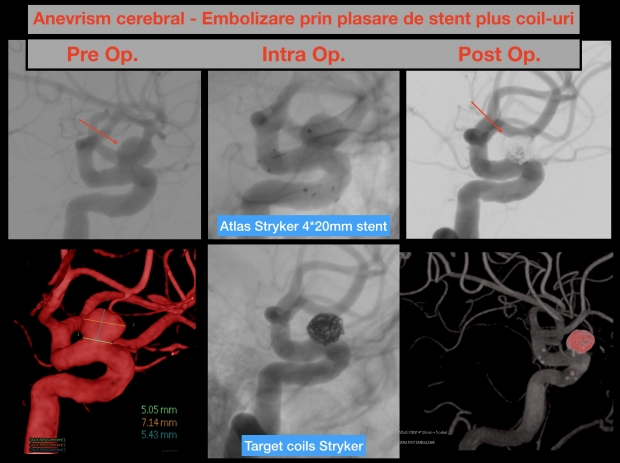

Cele mai multe cazuri de intervenţii minim invazive se referă la patologii dificile de trat în mod clasic, cum ar fi anevrismele cerebrale, accidentele vasculare ischemice sau stenoza cartodiană. De pildă, anevrismul cerebral beneficiază de o rată de succes impresionantă prin această tehnică.

Rata de ruptură a unui anevrism cerebral este estimată în studiile de specialitate ca fiind de circa 2-3% pe an. Cu cât pacientul este mai tânăr, cu atât riscurile de a experimenta o ruptură de anevrism şi, implicit, o hemoragie cerebrală sunt mai mari. Ruptura unui anevrism cerebral este în proporţie de 50% fatală pentru pacient şi supravieţuirea după o ruptură de anevrism cerebral lasă sechele neurologice în proporţie de 30-40%. Din acest motiv, embolizarea anevrismului cerebral, adică excluderea lui din circulaţia sanguină prin implantarea în sacul anevrismal de materiale specifice neuroendovasculare sau plasarea unui stent de tip Flow Diverter în faţa coletului anevrismal a devenit metoda de elecţie pentru tratarea acestei patologii. Principalul avantaj al metodei minim invazive este dat de siguranţa acestui tip de procedură (1,5-2% risc cumulat), în comparaţie cu rata de risc în cazul procedurilor de neurochirurgie deschisă, ce ajunge la 5-8%. Al doilea avantaj este acela al timpului scurt de spitalizare şi recuperare necesar post-intervenţie, de circa 3-5 zile.